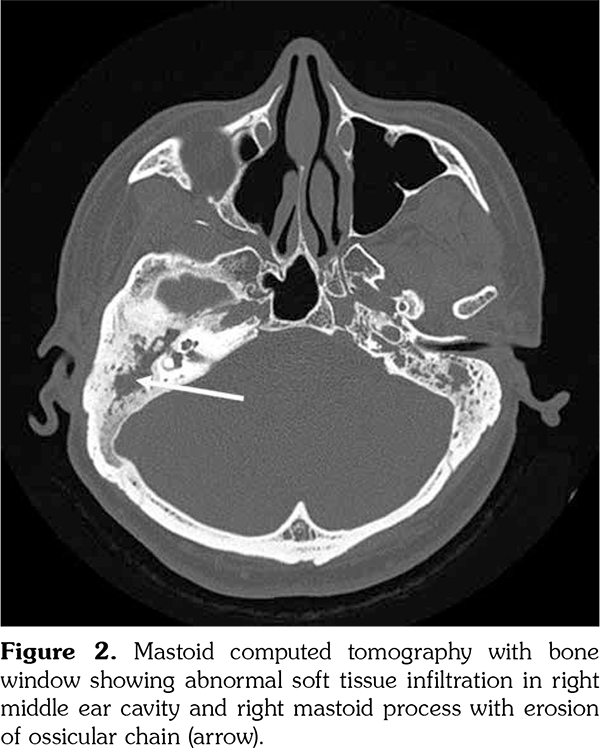

A 43-year-old male patient complained of right ear fullness that persisted for two years; he did not have type II diabetes mellitus, hypertension, or cholesteatoma. He was diagnosed to have otitis media with effusion; status post tympanocentesis was performed at another hospital at three different times; however, he suffered relapse soon after each treatment procedure. He then visited local medical doctors several times for tympanocentesis. In August 2011, he developed right hearing impairment for which he visited our hospital. An ear-nose-throat specialist confirmed right severe mixed hearing loss by pure tone audiometry (Figure 1). Mastoid computed tomography (CT) revealed abnormal soft tissue infiltration in his right middle ear cavity and right mastoid process with bony destruction (Figure 2). He received right tympanomastoidectomy in September 2011. His mastoid cavity was filled with granulation tissue and pus. His pathology report showed rich plasmacytoid cell infiltration. In the following two years, the patient did not visit our hospital, but he received several treatments for his ear from local medical doctors. His hearing, however, did not improve. Furthermore, the patient experienced an episode of seizure in January 2013. Magnetic resonance imaging of the brain revealed T2 hyperintensity and leptomeningeal enhancement (Figure 3), which indicated inflammation of the central nervous system. At this point, he revisited our hospital. Mastoid CT revealed abnormal soft tissue infiltration in his right middle ear cavity and right mastoid process with bony destruction. Hence, right modified mastoidectomy was performed and pulsatile granulomatous mass over his right mastoid cavity was found. His pathology report revealed plasma cell granuloma; however, the possibility of plasmacytoma was excluded on the basis of immunostaining results. In addition, it revealed positive IgG4 stain, with 59 IgG4- positive plasma cells in a high-power field (Figure 4). The percentage of IgG4-positive plasma cells in the field was approximately 45%. This finding led to the diagnosis of IgG4-RD, after which we initiated immunotherapy with cyclophosphamide and rituximab from April 2013 onward. Subsequently, the patient’s symptoms subsided and he did not require as frequent tympanocentesis as he did earlier. The erythrocyte sedimentation rate, IgG, and IgG4 levels also decreased after the treatment. The follow-up mastoid CT revealed remission of the pseudo tumor in his right middle ear cavity (Figure 5). A written informed consent was obtained from the patient.